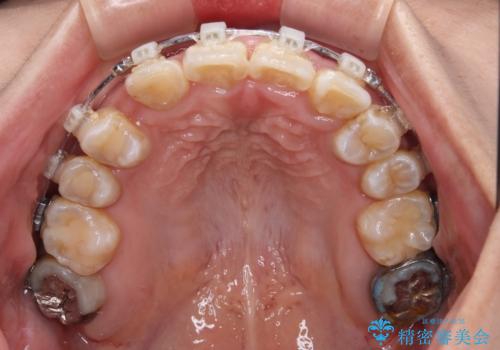

- 矯正装置

- 審美装置

下顎は第二小臼歯を抜歯したため、治療期間が長期化すると思われましたが、大臼歯が後方に傾斜していたため、容易にスペースを閉じることができ、2年強で治療を終えることができました。